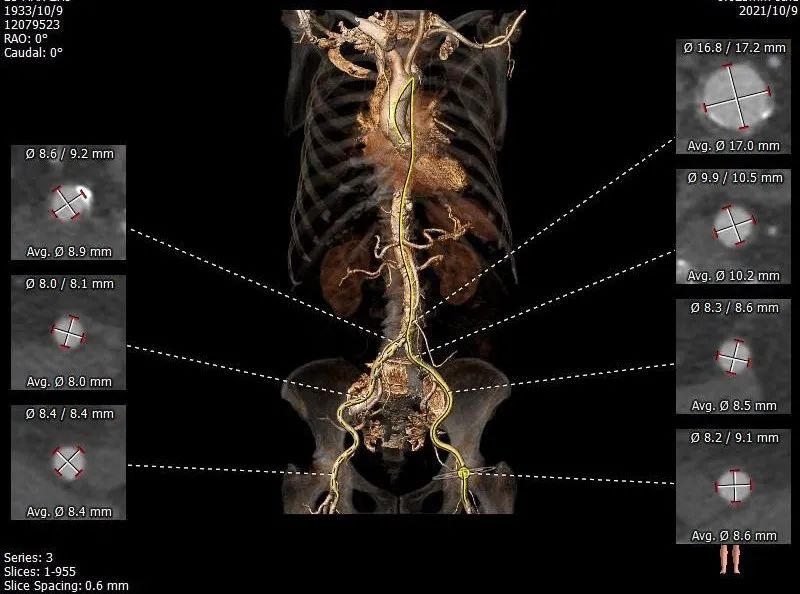

CT评估:三叶瓣,小瓣环,窦部较小,钙化不重,左室心腔小,冠脉高度可,双下肢入路可。

4. 全主动脉入路CT评估

本例患者为88岁高龄,外科开胸换瓣手术风险大,患者及家属希望尝试微创介入瓣膜置换。该患者主动脉根部术前CT评估提示瓣环较小,钙化较轻,窦部空间不大,左室心腔小,双下肢入路状态良好。为此我们选择最小型号23二代可回收TaurusElite瓣膜,采取经右股动脉极简式TAVR策略,不全麻、不插管、无导尿、无食道超声。经过吴永健团队熟练配合,瓣膜位置合适,无明显瓣周漏,达到预期效果,患者术恢复良好。